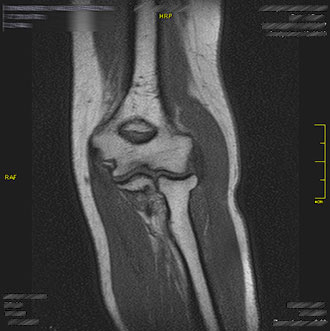

Das Kniegelenk gehört zu den am häufigsten untersuchten Regionen in der MRT.

Im Kernspin Zentrum Köln werden Traumafolgen, Osteochondrosen, Arthrosen oder Meniskusschäden präzise dargestellt.

Die MRT hilft, Risse, Schwellungen oder Knorpelschäden zuverlässig zu erkennen – eine wichtige Grundlage für orthopädische und chirurgische Therapieentscheidungen.